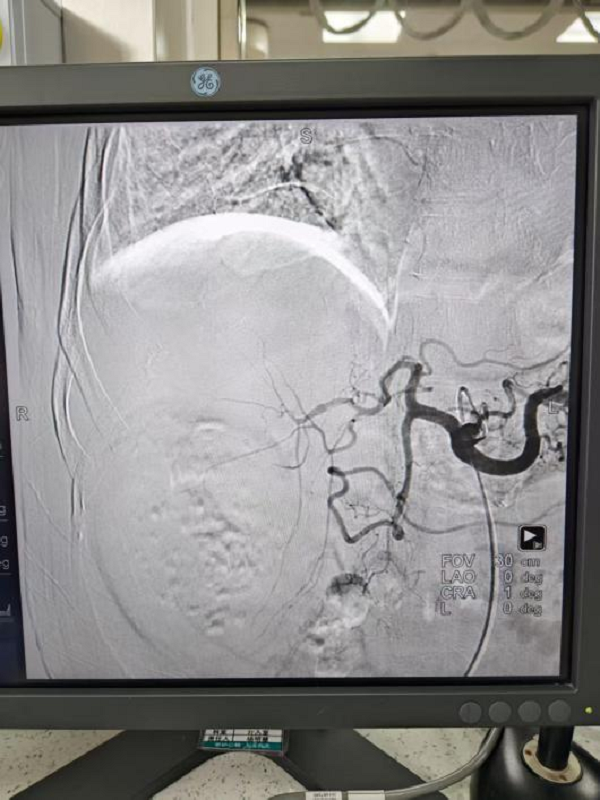

3. 经导管肝动脉化疗栓塞术(TACE):患者是一名73岁的男性,检查发现肝占位性病变50天,腹部CT可见右肝1个大小约8.5cm病灶,肝左叶及右叶均可见一0.5cm大小病灶,考虑肝恶性肿瘤伴肝内转移,于2026年2月14日在宜春市人民医院行经导管肝动脉化疗栓塞术。于2026年3月15日在我院由郭陵副主任医师、江福生主任医师(宜春市人民医院) 龙旺主治医师在局麻下行经导管肝动脉化疗栓塞术,手术顺利,患者术后无明显并发症。较大的肝恶性肿瘤无手术切除指征,可行经导管经导管肝动脉化疗栓塞术通过缩小肿瘤,寻求手术机会,或者延长患者生命,改善患者生活质量。